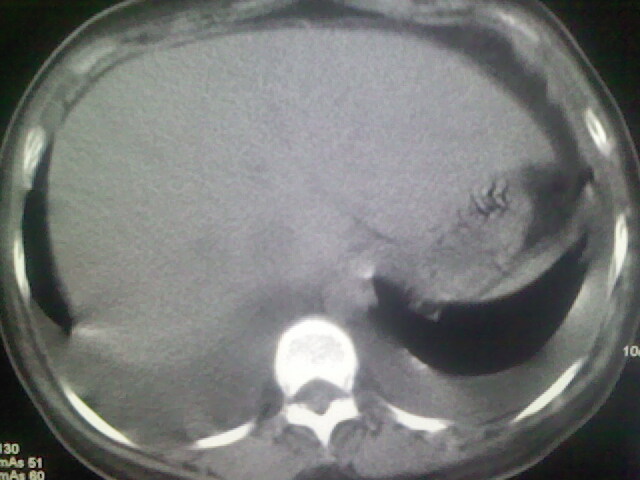

女,24,剖腹产后,突觉胸痛,干咳,不能平卧

双肺“肺泡性肺水肿” “胸腔积液”!

考虑肺梗塞、肺水肿,双侧胸腔积液

肝脾大,双侧胸腔积液,双肺水肿,肺动脉[包括远端小动脉],左右心房,左心室增宽,右心室主动脉无明显改变,符合左心功能不全征;;建议除外二尖瓣关闭不全,扩张性心肌病

临床资料及影象表现支持围产期扩张型心肌病改变,心衰。

考虑产后心肌病,心功能不全,肺水肿,双侧胸腔积液。